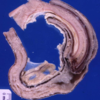

What lesion is shown here?

enamel hypoplasia